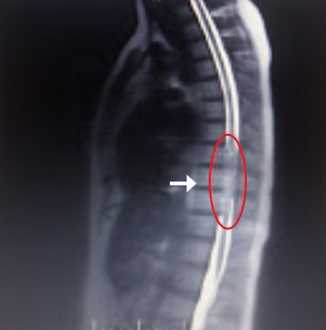

This is me. Well, me and a visitor. A creepy dude that doesn’t belong, taking up some prime real estate inside my spinal cord. Squishing all the nerves that are entitled to a peaceful and roomy existence. That big blob (circled in red), isn’t supposed to be there.

He’s known to the medical community as an intramedullary ependymoma in my thoracic spine (more precisely … inside the spinal cord in the thoracic region). To me he’s Herm the Worm – a guy that took up residence 7-10 years ago and got all comfy cozy and started to grow.